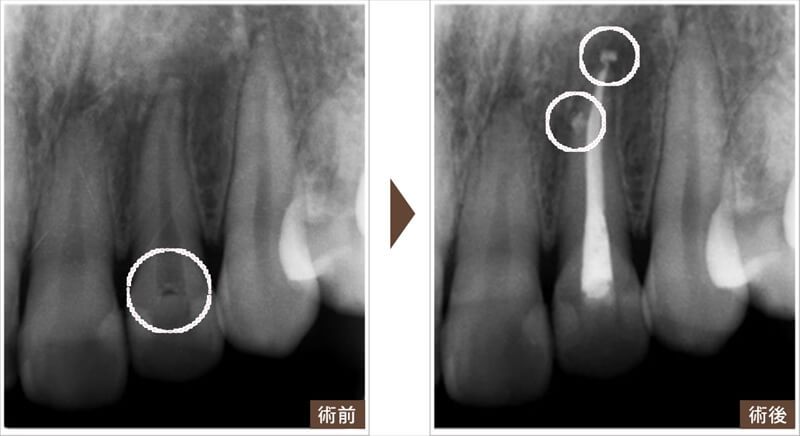

根の治療(根管治療)の一例

虫歯が大きく神経まで達した場合

以前の治療で完全に虫歯が除去できておらず、詰め物の下で虫歯が再発し、神経(歯髄)まで進行してしまったため来院された患者様です。感染した神経を丁寧に除去し、歯の中を洗浄することで、複雑な根の先まで綺麗に薬剤を詰めることができました。

根の先が化膿(膿んでしまった)した場合の処置

虫歯が進行し、根の先までばい菌が入り込み、歯ぐきが腫れたことで来院された患者様です。しっかりと歯の中を洗浄し、根の先までお薬を入れることで、歯茎の腫れも改善されました。